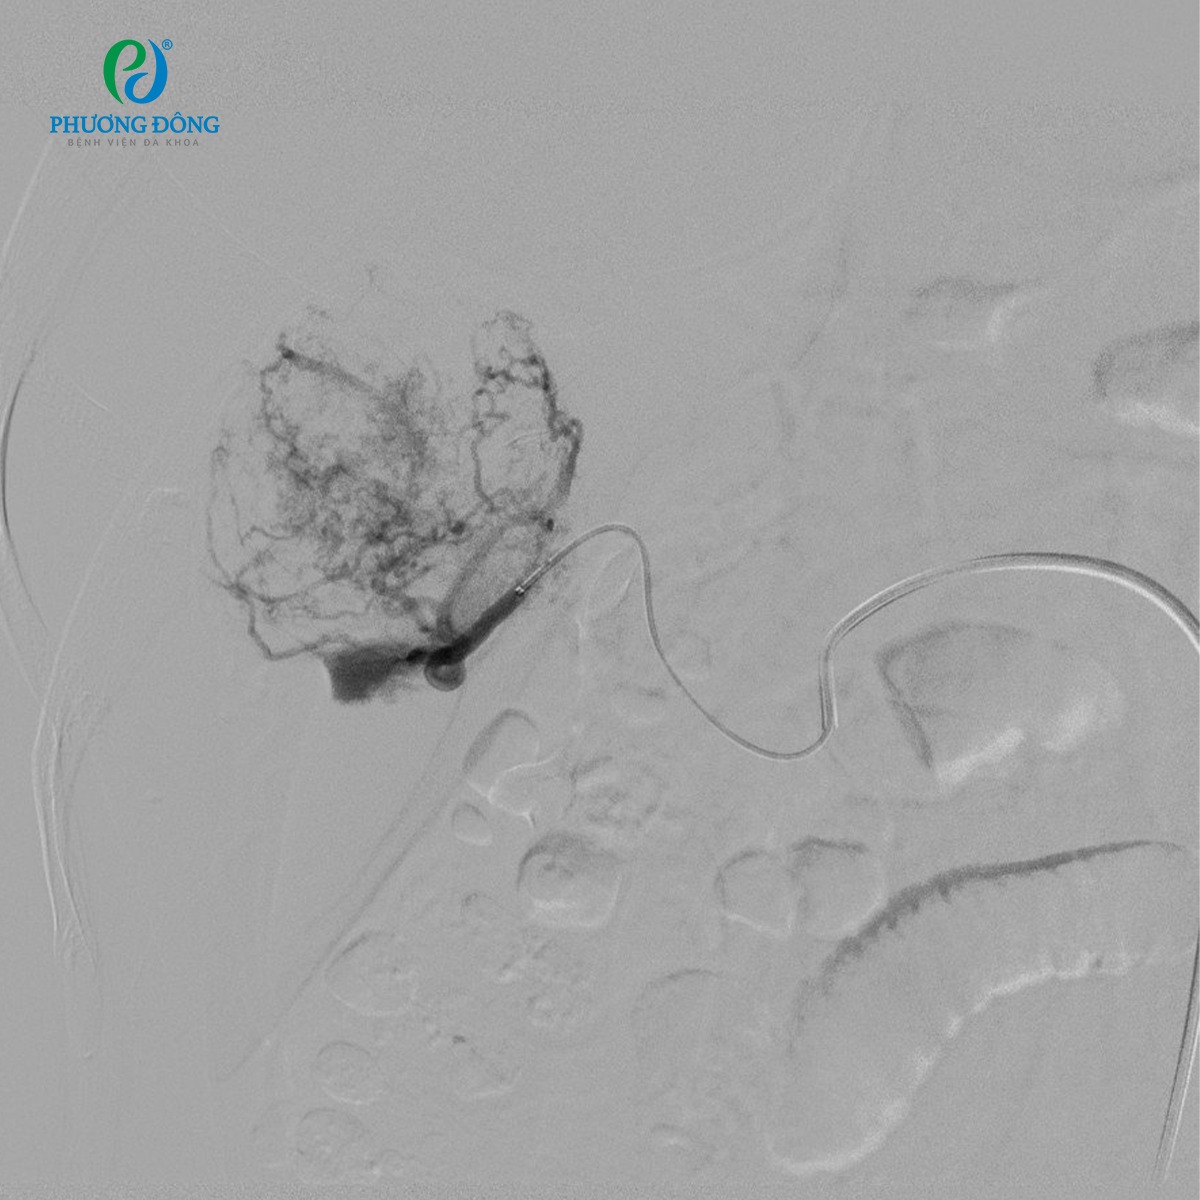

- Chụp mạch chọn lọc xác định chính xác vị trí ổ giả phình và nhánh động mạch nuôi u

- Dùng microcatheter tiếp cận mục tiêu ở mức độ siêu chọn lọc

- Nút tắc ổ giả phình và mạch máu nuôi u bằng vật liệu chuyên dụng, loại bỏ hoàn toàn nguồn máu nuôi khối u.

- Ổ giả phình được nút tắc hoàn toàn

- Ngừng cấp máu cho toàn bộ khối u